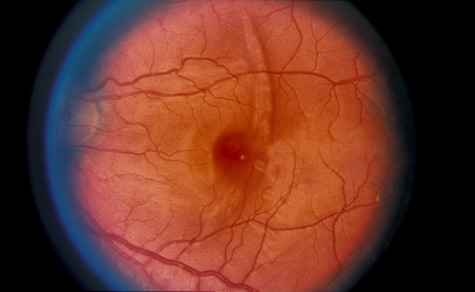

Commotio retinae (Latin, meaning retinal contusion) is a contrecoup injury. It can occur peripherally (Fig. 8) or centrally, in which case it is called Berlin's edema (Fig. 9). Immediately and for several hours after the trauma, the retina appears normal, although the patient may complain of decreased vision. Thereafter, the outer layers of affected retina become opaque. On fluorescein angiography, the opaque retina blocks background choroidal fluorescence, and in most cases there is no leakage into or under the retina (Fig. 10). For years, clinicians had difficulty explaining this blockage, because leakage is expected in conditions with edema. It was then shown in experimental animals and in human autopsy eyes that Berlin's edema is not true edema. The retinal opaqueness is the result of intracellular edema and fragmentation of the photoreceptor outer segments and intracellular edema of the underlying pigment epithelium. There is little or no intercellular fluid.66–69

Fig. 8. Peripheral commotio retinae. The retinal blood vessels are clearly seen because the retinal whitening is in the outer retinal layers.

Fig. 9. Commotio retinae in the macula (Berlin's edema). The visual acuity was 20/25 at the time of the photograph and later improved to 20/15.

Fig. 10. A: Commotio retinae in the macula. B: On the angiogram there is no leakage in the area of commotio retinae.

The visual acuity in commotio retinae varies from 20/20 to 20/400 and does not always correlate with the degree of retinal opacification. There is no known treatment. The prognosis is usually excellent except in cases with associated subfoveolar choroidal rupture and in cases with choroidal rupture with subfoveolar hemorrhage. Poor visual recovery can also be expected in cases with severe retinal pigment epithelial damage. Serous retinal detachment (Fig. 11) signals this condition, which can be confirmed by leakage of fluorescein into the subretinal space.70